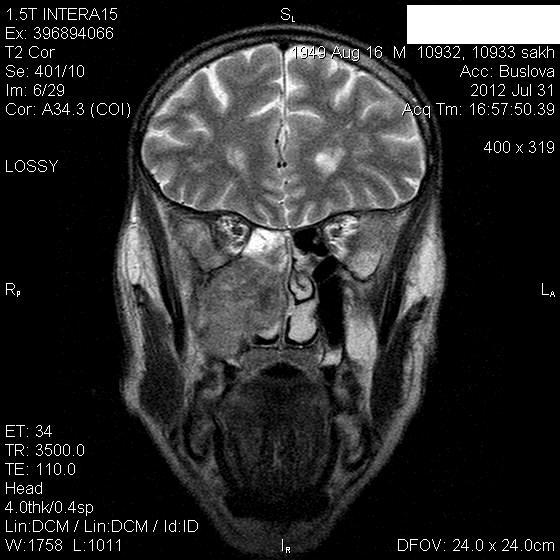

Мужчина лечился около месяца от правостороннего гайморита.Неоднократно пунктировали.Выписался из стационара, через 3 дня попал к другому ЛОР-врачу, который направил пациента на КТ, но волею судеб он оказался у нас.Визуально: незначительный экзофтальм справа, отек скуловой области, который периодически исчезает.Пыталась добыть его рентгеновский снимок пазух через знакомого отоларинголога, вхожего в лечебное учреждение, где лечился пациент-бесперспективно ( просто исчез, со слов лечащего врача-обычный правосторонний гайморит), хотя просила всего-то для себя, чтобы самой в такую ситуацию не попасть.

В заключение выставила объем.

Где-то в душе грелась мысль о нагноившейся гематоме, пока не показала исследование нашему отоларингологу, который пытался помочь в поиске рентгенограммы.

Нашла похожее образование в книге Г.Труфанова как плоскоклеточный рак.

Вот буквально две недели назад у нас был почти аналогичный пациент , он тоже длительно ходил по врачам и лечился прогреваниями от стреляющих в висок болей. Пришел на МРТ случайно -отправила к ЛОР и челюстно-лицевым хирургам. Думаю и здесь есть озлокачествление хронического процесса. Трудно сказать есть ли деструкция медиальной стенки пазухи , деформация точно есть.